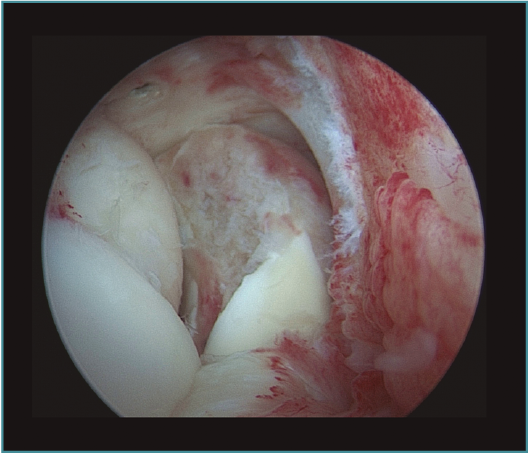

Método: hemos revisado 38 pacientes con codo rígido postraumático o degenerativo que se trataron mediante artrolisis artroscópica entre 2013 y 2016, con un seguimiento medio de 25 meses (38-15). Según la etiología de la rigidez, clasificamos a los pacientes en 2 grupos: grupo 1, los pacientes con rigidez por patología degenerativa del codo, y grupo 2, los pacientes con rigidez postraumática. Clasificamos la rigidez siguiendo la escala de Morrey y utilizamos la escala funcional Mayo Elbow Performance Index (MEPI), que evalúa el dolor, la movilidad, la estabilidad y la función del codo pre- y postoperatoriamente. Describimos los procedimientos artroscópicos realizados en cada paciente, que incluyen la sinovectomía, el desbridamiento de tejido fibroso, la capsulectomía anterior y/o posterior, la resección de osteofitos en la parte anterior y posterior del codo, la extirpación de cuerpos libres y la liberación “abierta” del nervio cubital.

Method: a review was performed on 38 patients with stiff elbow due to degenerative or post-traumatic reasons, and who were treated by arthroscopic arthrolysis between 2013 and 2016, with a mean follow-up of 25 months (38-15). Elbow stiffness was classified following the Morrey scale and the Mayo Elbow Performance Index (MEPI) functional scale was used to evaluate pain, mobility, stability and elbow function pre- and post-operatively. The arthroscopic procedures performed on each patient are described, including synovectomy, debridement of fibrous tissue, anterior and/or posterior capsulotomy, resection of osteophytes in the anterior and posterior part of the elbow, extirpation of loose bodies and open release of the ulnar nerve.